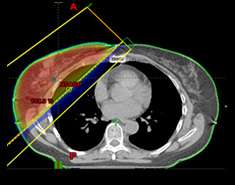

Whole breast radiation therapy (fig 1)

- Standard fractionation – 6.5 weeks

- Hypofractionation – 3-4 weeks